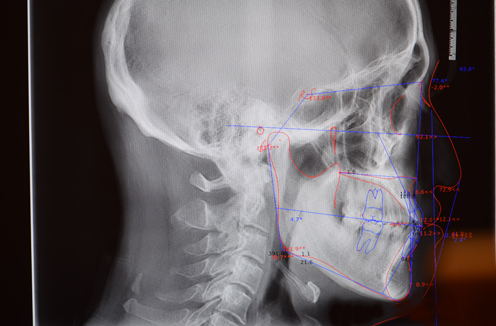

디지털 세팔로 X-ray 및 모의시술 프로그램

웰플란트 치과는 교정 진단시에 얼굴 측면 x-ray촬영이 가능한 디지털 세팔로 x-ray 와 컴퓨터 진단 프로그램을 보유하고 있스빈다. 교정전후 골격 및 연조직 분석, 교정 후 안모 예측 시 뮬레이션은 정확한 진단 및 최적의 치료계획 수립을 가능하게 합니다.